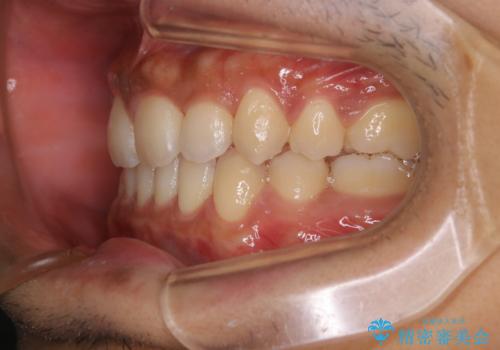

インビザライン単独でここまでできる!!抜歯矯正

1日20時間以上、正しくインビザラインを使用して頂いたおかげで、ワイヤーに切り替えることなく矯正治療を終了することが出来ました。周囲からも歯並びがすごく綺麗になったと言われたのことで大変ご満足いただけました。